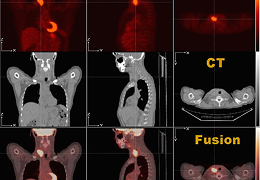

DTI

Single-click Fiber Tracking.

Accelerate your DTI post-processing workflow with fully automated tractography.

Reconstruct multiple clinically significant white matter tracts with one click.

Review all your tracts over any Perfusion or fMRI related map.